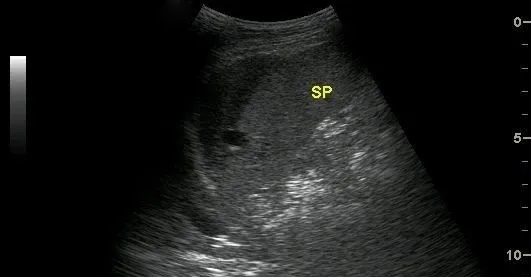

超聲表現(xiàn)為:脾臟實質(zhì)內(nèi)探及邊界清楚的非均質(zhì)區(qū),單發(fā)或多發(fā),如伴有較大血腫時,非均質(zhì)區(qū)內(nèi)可探及不規(guī)則或類圓形無回聲區(qū),透聲較差。

中央型脾破裂

是指脾臟實質(zhì)內(nèi)部的出血,在脾臟內(nèi)形成血腫。